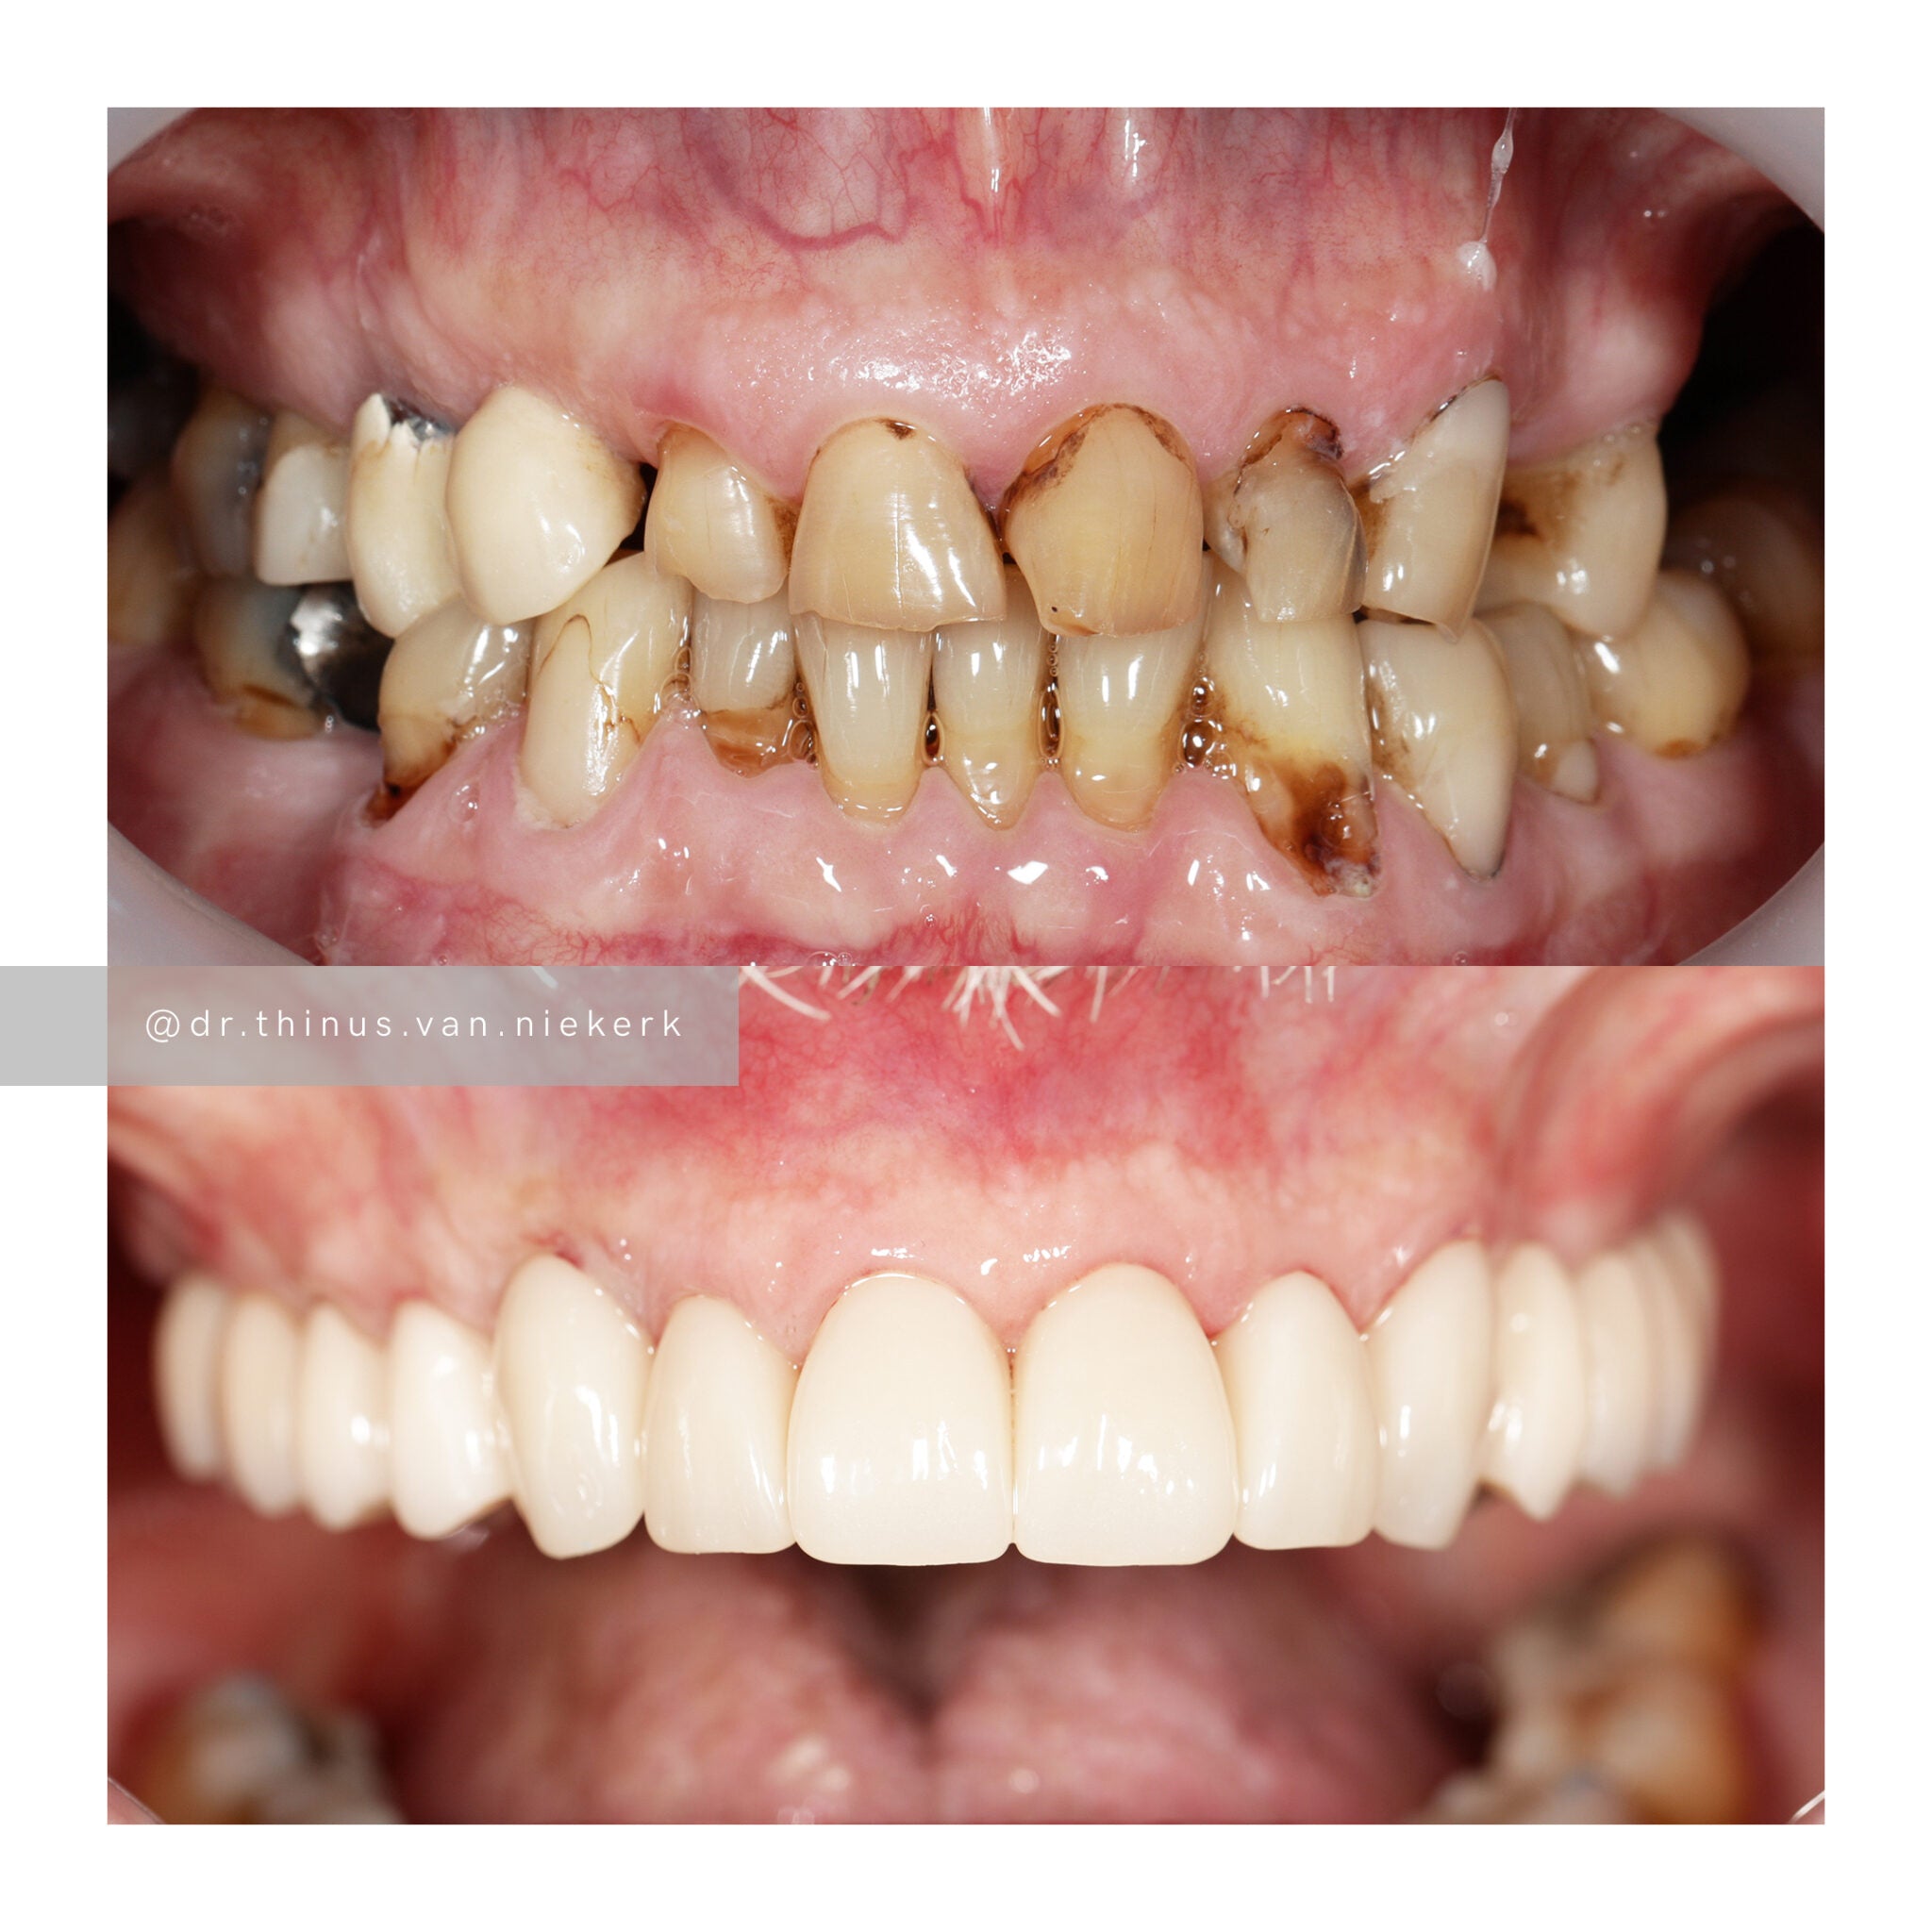

Case 2

TREATMENT OBJECTIVE

Our aim was to remove all elements of infection and disease and to restore function as quickly as possible. The complete case was digitally planned prior to the day of surgery. Six fully-guided implants were placed during a two-hour morning surgery. An immediate implant-supported prosthesis was delivered on the same day.

COMMENTS

This case demonstrated the power and effectiveness of digital implant-surgery planning and CAD design software.